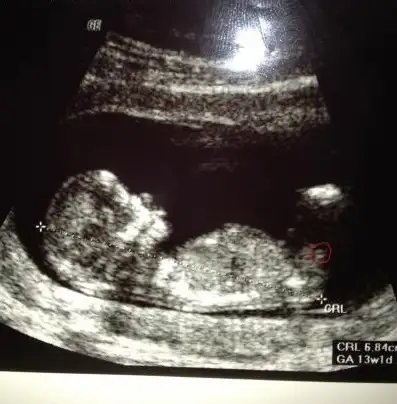

merhaba tekrar. Sizce yuvarlak içine aldığım şey nub mu arkadaşlar? nub ise bakar mısınız? tşk

canım bıde buna bakarmısın nolur 12 + 5 Eki Görüntüle 857255 Eki Görüntüle 857256